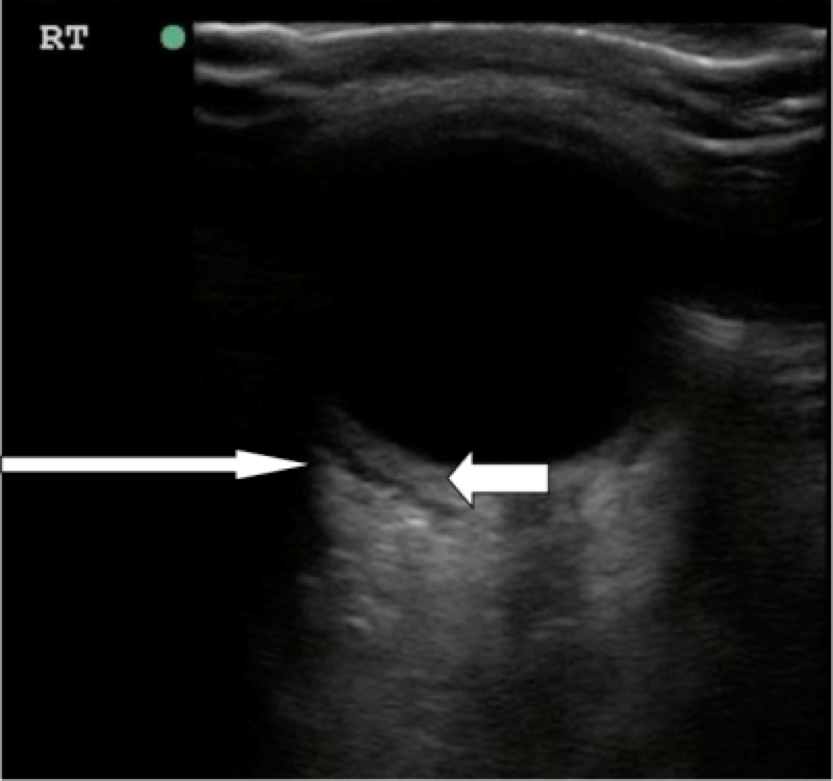

- Figure 10. Orbital cellulitis. Long arrow shows hypoechoic rim concerning for postseptal fluid tracking posterior to the globe. Short arrow shows thickening of the posterior segment of the eye.12 (Source: Seif D et al.13)